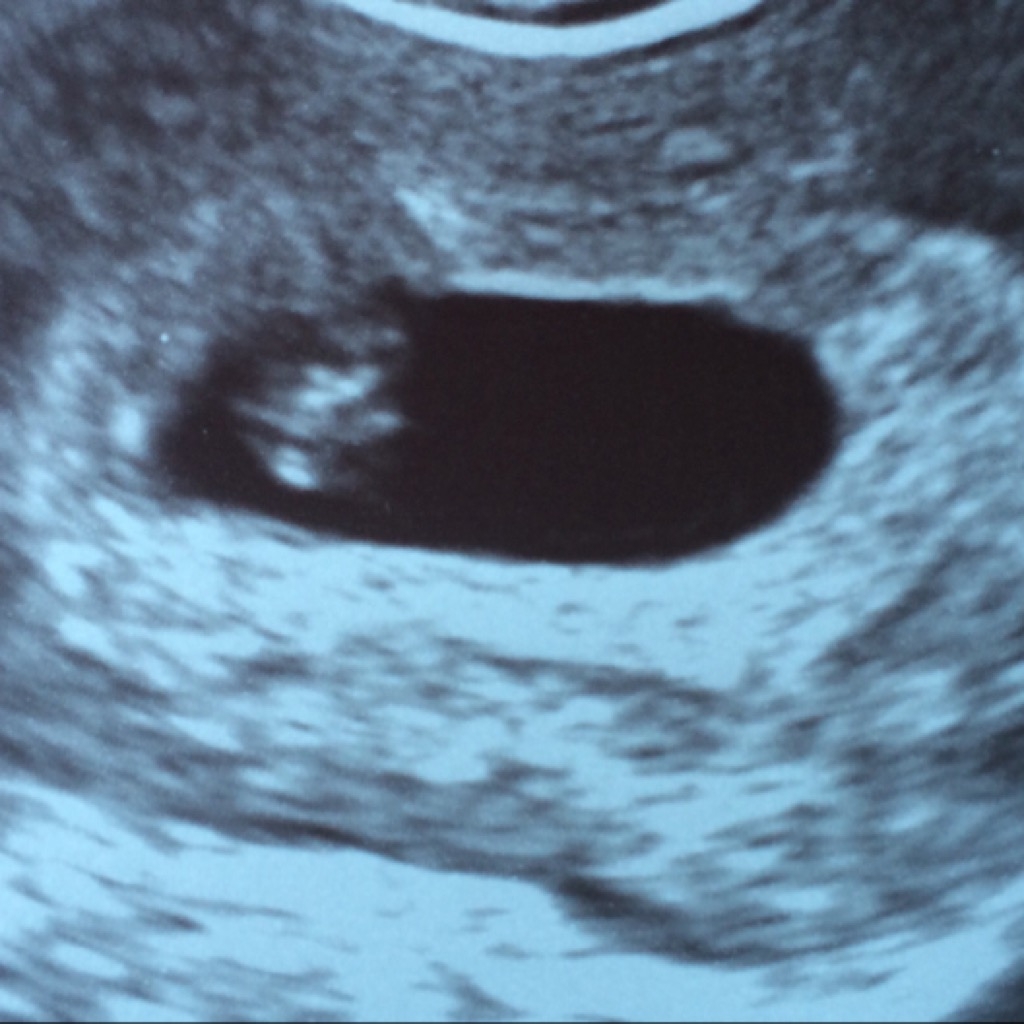

This was at 4+4, but the gestational sac (pretty much all you can see) measured at 5+2, so they think I ovulated a few days early. You can't see much, but I still love being able to see what's going on!

SaveSaveThis was at 4+4, but the gestational sac (pretty much all you can see) measured at 5+2, so they think I ovulated a few days early. You can't see much, but I still love being able to see what's going on!